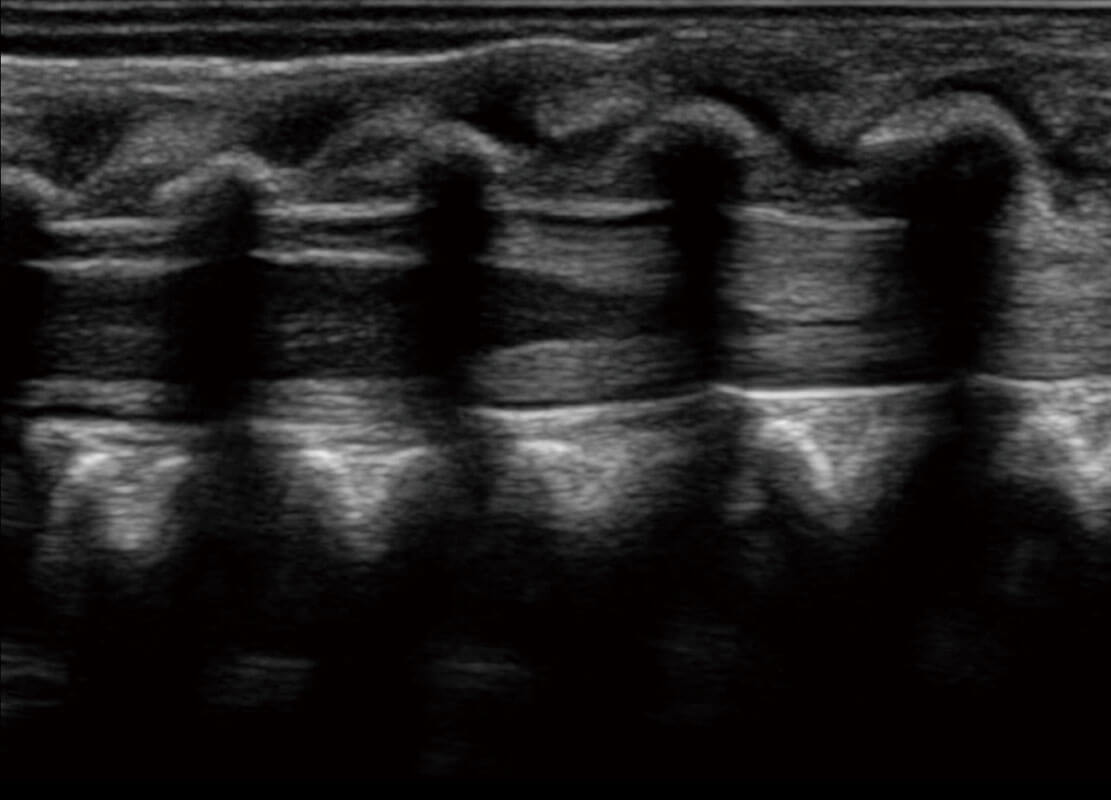

P60搭载一系列胎儿心脏成像技术,实现精细的胎儿心脏评估。

四腔切面

四腔心血流